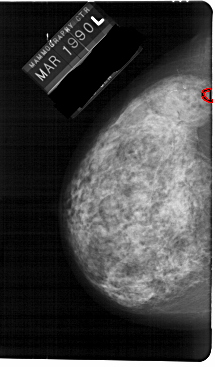

A_1148_1.LEFT_CC

LEFT_CC LINES 5491 PIXELS_PER_LINE 3211 BITS_PER_PIXEL 12 RESOLUTION 43.5 OVERLAY

FILE: A_1148_1.LEFT_CC.OVERLAY

TOTAL_ABNORMALITIES 1

ABNORMALITY 1

LESION_TYPE CALCIFICATION TYPE PLEOMORPHIC DISTRIBUTION CLUSTERED

ASSESSMENT 4

SUBTLETY 2

PATHOLOGY MALIGNANT

TOTAL_OUTLINES 1

BOUNDARY